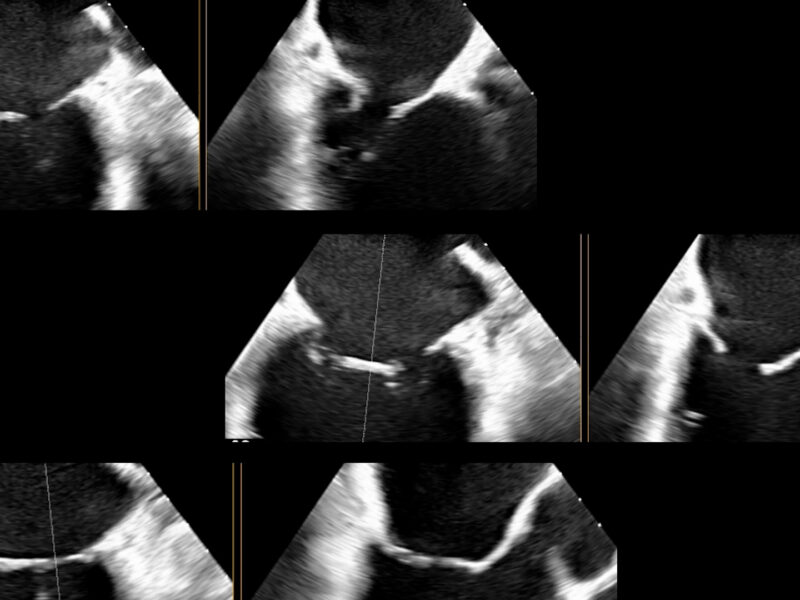

Le Linee Guida comprendono una sezione iniziale dedicata agli aspetti generali delle malattie cardiovascolari in gravidanza. In essa si sottolineano l’importanza dell’età della madre e soprattutto della presenza pre-gravidanza di fattori di rischio cardiovascolare (diabete, ipertensione e obesità, tra i più comuni) come componenti favorenti lo sviluppo di malattie cardiovascolari in gravidanza. Tra questi, hanno il maggiore riscontro i disturbi ipertensivi, insieme alle patologie cardiache congenite. Al riguardo si raccomanda di effettuare, prima dell’inizio della gravidanza, quando opportuno, approfondimenti diagnostici specifici, come per esempio un’ecocardiografia, in aggiunta all’ECG. Un riferimento sul tema è anche la “modified WHO classification of maternal cardiovascular risk – mWHO”, inserita nelle Linee Guida stesse, e che raccomanda di fare sempre una valutazione cardiovascolare pre-gestazione in tutte le donne con patologie correlate. Inoltre, il counselling genetico viene sempre raccomandato nelle donne con patologie cardiovascolari congenite, aritmie congenite, cardiomiopatie, aortopatie o malformazioni cardiovascolari su base genetica.

La diagnostica cardiovascolare in gravidanza richiede ovviamente particolari cautele per evitare esposizioni ad agenti fisici (ad es., radiazioni ionizzanti) e chimici potenzialmente dannosi per il feto. Al riguardo, la risonanza magnetica nucleare senza gadolinio può essere utilizzata se l’ecocardiografia non risulta sufficiente per la diagnosi. Dato che parliamo di unità materno-fetale, non dimentichiamo anche la salute cardiovascolare del feto, che va monitorata secondo le esigenze, ad esempio con ecocardiografia fetale.